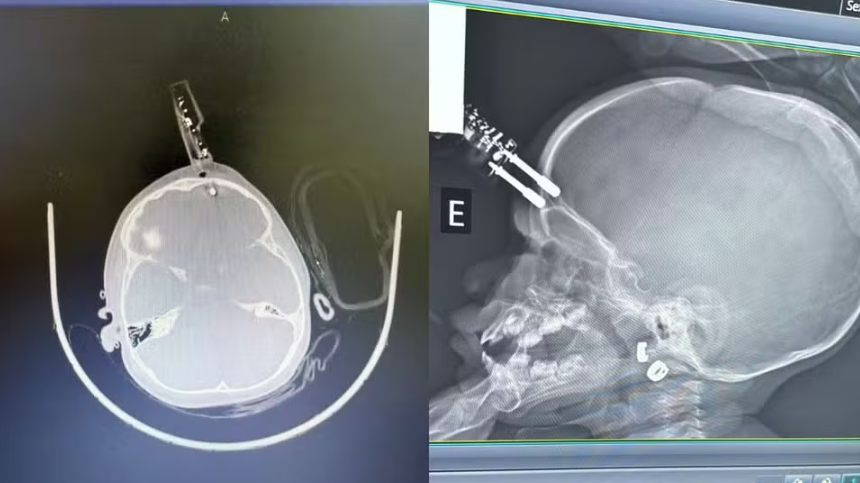

A menina passou por cirurgia de emergência no Complexo de Saúde São João de Deus, onde o objeto foi retirado e a área, reconstruída. O atendimento rápido evitou hemorragia e infecção, incluindo o risco de meningite.